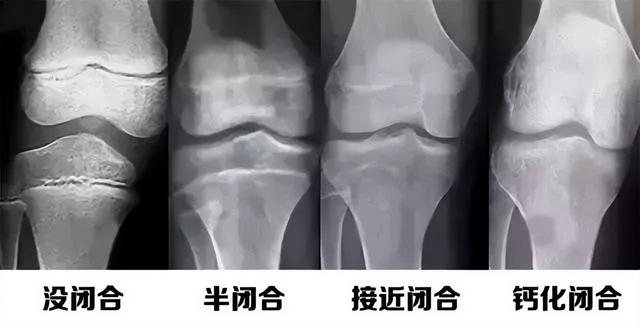

三、骨骺线什么时候闭合?

骨骺线闭合分为生理性闭合和病理性闭合。

1.生理性闭合:在正常生长发育的情况下,在人体激素的调节下,骨骺线会逐渐闭合。

女生进入青春期较早,所以大多数女性骨骺线会在15-17岁时闭合;

男生骨骺线的闭合时间一般在17-19岁左右。

骨骺线闭合后,身高基本不会有特别大的变化。